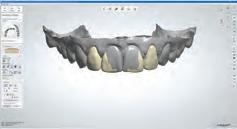

A 31-year-old woman presented with cosmetic concerns regarding her smile and requested a conservative enhancement. After clinical and radiographic analysis, digital 35mm photographs were taken and reviewed by the restorative clinician, technician, and surgeon (Fig 1). A digital impression was taken of the maxillary and mandibular arches using an intraoral scanner (Trios 3, 3Shape; Fig 2), and a smile design was developed with NemoSmile Design 3D software (Nemotec; Fig 3a). This allows for a facially driven smile frame to be created using reference lines of facial and smile proportions and natural teeth shapes and textures from the digital library (Fig 3b).

After developing the simulated mock-up, a 3D-printed resin model was created using CAD software (Fig 4a), and a clear PVS matrix (Exaclear, GC America) was fabricated to replicate the printed diagnostic wax-up using a nonperforated tray (Fig

4b). This matrix was used to create an intraoral motivational mock-up with bis-acryl composite (Luxatemp Ultra, DMG). This additive mock-up provides the interdisciplinary team with an intraoral translation for evaluation (Fig 5). Upon evaluation of the digital smile frame and the clinical translation, it was determined that multiple esthetic and restorative requirements were necessary for an optimal biologic framework, and the interdisciplinary team determined the best sequence for these procedures. The patient was presented with the interdisciplinary treatment possibilities that included restoring the maxillary anterior teeth and premolars with a minimally

invasive preparationless procedure or with less conservative veneer preparations. The restorative materials discussed included injectable resin composites and ceramic (ie, feldspathic, pressable, machinable). For an optimal biologic framework and health, it was determined that connective tissue grafting would be necessary for treatment of the recessiontype defects on the maxillary left central and lateral incisors, canine, and premolars. The patient opted for the conservative preparationless composite veneers using the injectable resin technique followed by a connective tissue surgical procedure using the tunneling technique.